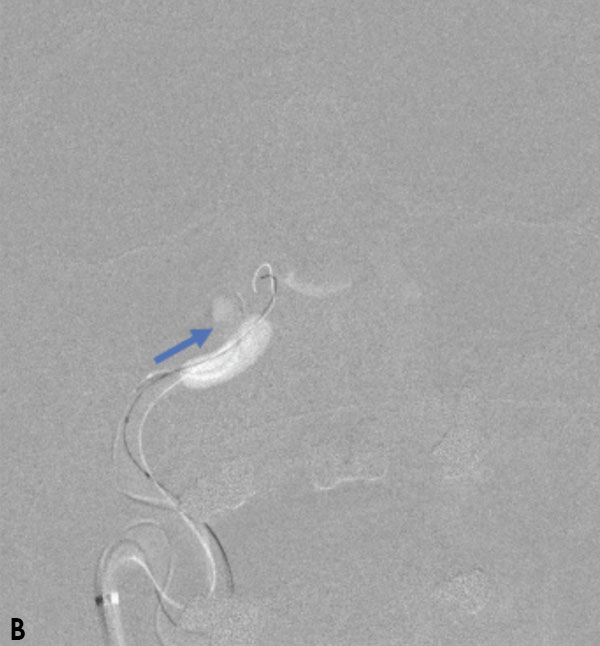

Collateral venous drainage into the orbit and skull base was observed (Figure A). After successful cannulation of the direct aperture between the right carotid artery and the cavernous sinus, balloon-assisted coil embolization of the posterolateral compartment was performed until the fistula was closed (Figure B and C). He experienced immediate cessation of his pulsatile tinnitus with an early improvement of the right VI nerve palsy and near-complete recovery of his vision within 6 weeks

Figure: (A) Right ICA Cavernous Fistula with Venous Shunting (B) Balloon Assisted Coil Embolization (C) Fistula Cured Post Embolization